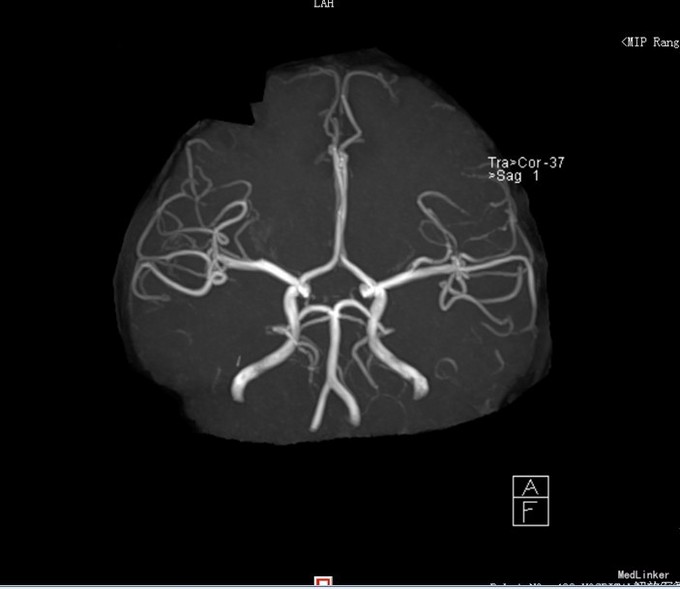

患者,男,14岁,患者自2周前不慎因外伤后出现头痛、头晕,为持续性钝痛,以后枕部为主,无发热畏寒,无视物模糊,无胸闷气短等不适,当时未引起足够重视,后患者感症状持续存在,遂告诉家人,家人送到我院门诊就诊,查头颅CT示:1、双侧大脑半卵圆中心区见多发斑片状低密度影,考虑血管间隙扩大可能,建议MRI复查;2、双侧额窦、筛窦炎。为进一步检查及治疗入院。患者目前精神欠佳,体力下降,食欲正常,睡眠正常,体重无明显变化,大便正常,排尿正常。既往体健。

患者目前诊断:1、脑外伤后综合征;2、半卵圆中心区血管间隙扩大;给予改善循环、营养神经等对症治疗,患者头痛、头晕症状明显好转。

经过1周治疗,患者头痛头晕症状基本消失。目前半卵圆中心区血管间隙扩大需要3月后复查。目前血管间隙扩大与此次外伤间有关系吗?其血管间隙扩大的机制是什么呢?